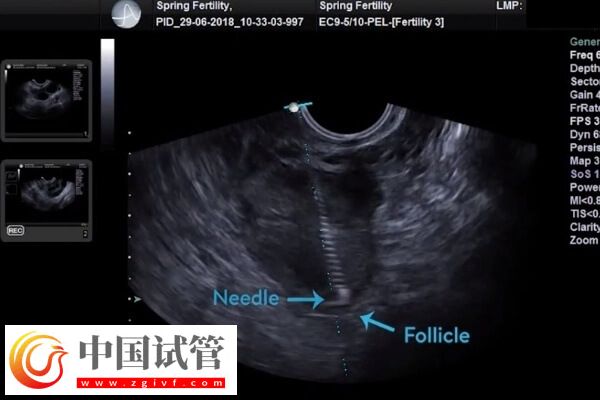

试管婴儿诊疗中需要从卵巢内把卵子取出来,而因为卵巢促排以后体积增大,部分患者会出现腹水的现象,为了不影响后续胚胎的种植,很多人会比较担心腹水的影响,以及腹水应该如何处理。